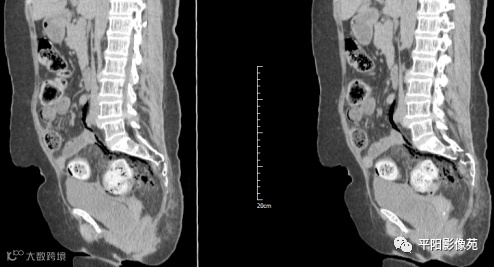

影像表现:乙状结肠前方可见不规则条状软组织密度影,边界不清,内见点状高密度;乙状结肠周围及骶前可见多发气体密度影。

影像表现:主要特点是腹腔内游离气体,可见肠壁增厚,边缘模糊,周围脂肪间隙模糊不清,并见不规则片状低密度,有粪石漏出时可见结节状高密度。